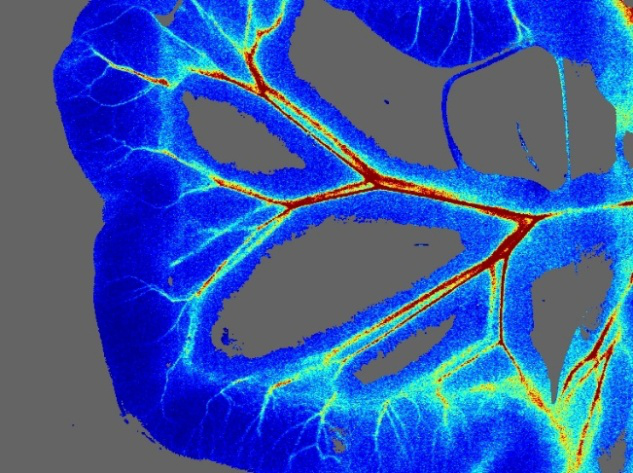

組織血流血氧實(shí)時(shí)成像系統

moorO2Flo-2 是一個(gè)獨特的成像系統,可以同時(shí)對組織灌注、組織含氧血紅蛋白、脫氧血紅蛋白的變化進(jìn)行實(shí)時(shí)圖像獲取。

該系統將用于灌注成像的高端激光散斑對比技術(shù)與用于氧合變化成像的反射光譜相結合,提供了兩種實(shí)時(shí)同步實(shí)驗的數據。

組織血流血氧實(shí)時(shí)成像系統測得的血流圖可直觀(guān)顯示組織血流和血氧的分布狀況,廣泛應用于組織缺血性疾病以及相關(guān)的藥物研究。

器官血流

moorFLPI可以用于評價(jià)缺血性肝臟疾病、胃部疾病以及腸系膜等領(lǐng)域的疾病研究。